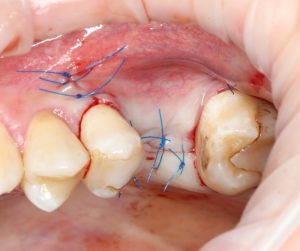

Теперь швы:

Контрольный снимок — ортопантомограмма:

Рекомендации после операции можно посмотреть здесь>>

Первый этап имплантологического лечения завершён.

К следующему этапу мы подойдём через 3-4 месяца. Этого времени достаточно для интеграции имплантата и регенерации субантрального пространства после синуслифтинга.